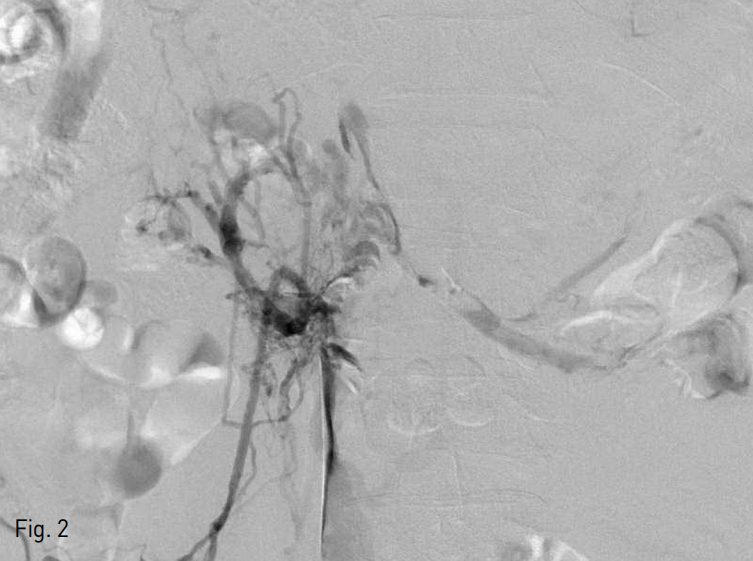

Fig. 4

A. Follow up venography after overnight thrombolysis shows Remnant thrombosis in infrahepatic IVC.

B. Aspiration thrombectomy was performed again.